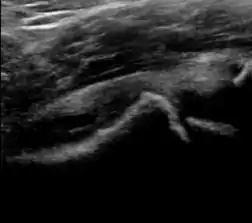

During childhood, ultrasound is a quick method to assess hip pain and quite often may be used to avoid use of irradiating techniques, such as radiography or CT. Ultrasound allows evaluation of joint effusion, synovial thickening and neovascularity, the bone/cartilage contour, and the femoral head-neck alignment. Although sonography is extremely sensitive in detecting increased synovial fluid, it is nonspecific and cannot be used with accuracy to determine the type of fluid. Transient synovitis of the hip, despite being the most frequent cause of pain in children between 3 and 10 years, remains a diagnosis of exclusion. It usually shows anechoic fluid, but echogenic fluid can also be found. The effusion is considered pathologic when it is measured at >2 mm in thickness. The differential diagnosis is wide, including osteomyelitis, septic arthritis, primary or metastatic lesions, LCPD, and SCFE. Discrimination from septic arthritis is challenging, often requiring joint aspiration. In septic arthritis, US is able to demonstrate a hip joint effusion, synovial thickening, and cartilage damage, although the appearances are nonspecific.[1]

A step between the head and the physis can be detected in children with SCFE, while abnormalities in the femoral head contour may suggest the presence of LCPD. In both cases, radiographs are mandatory to confirm diagnosis and severity (Figure 12).[1]

Figure 12:

Normal ultrasound appearance of the femoral head-neck junction.

Joint effusion in transient synovitis of the hip.

Flattening of the femoral head in a patient with Perthes disease.

Step in the femoral head-neck junction in a patient with SCFE.